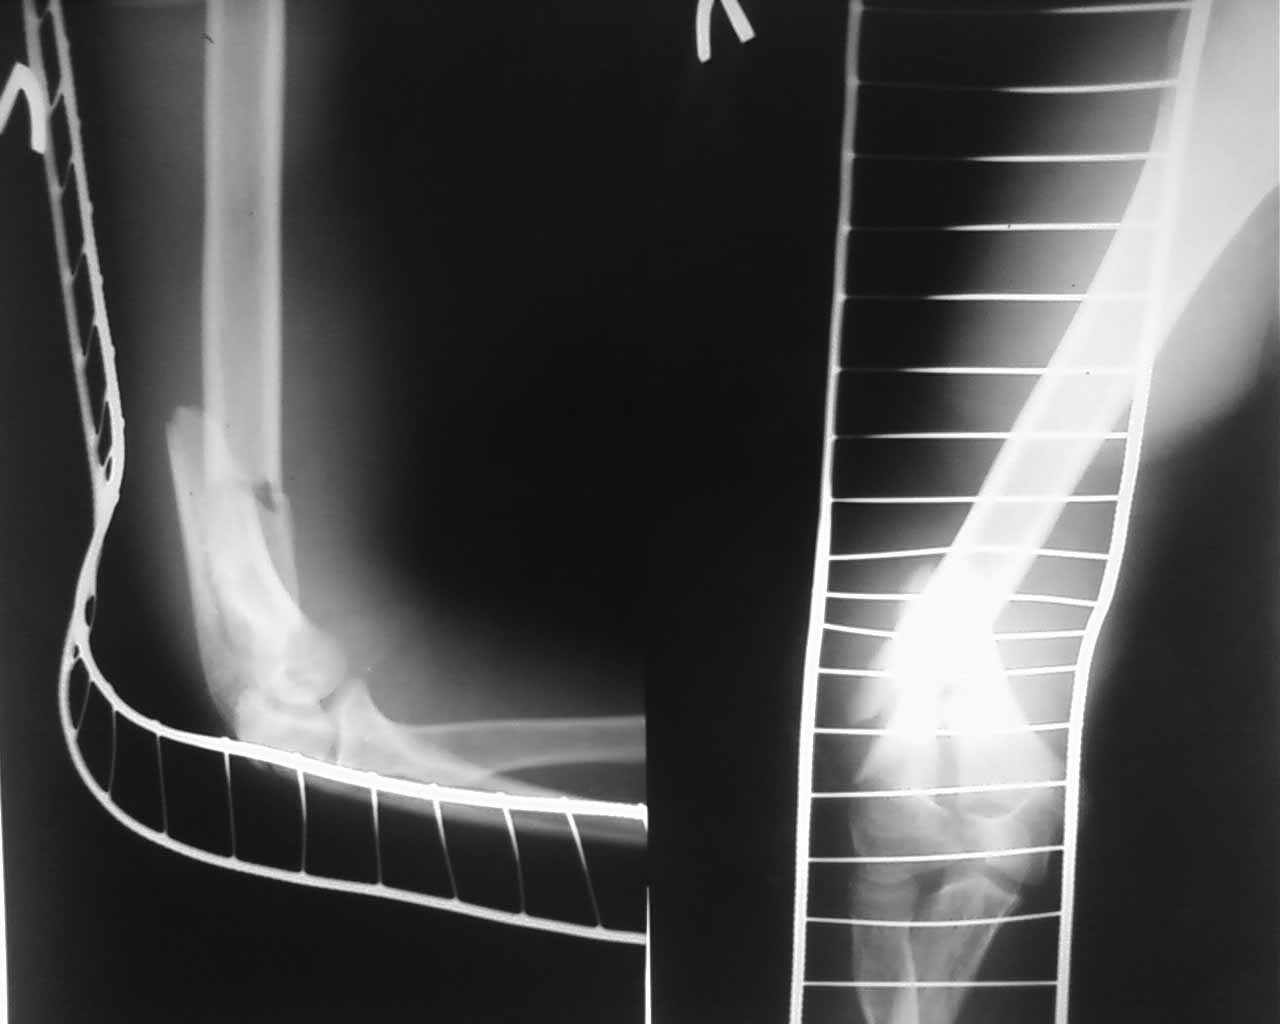

открытый т- образныйй внутрисуставной перелом дистального метаэпифиза плеча у ребёнка 13 лет |

В отделение травматологии и ортопедии поступил подросток 13 лет за 2 часа получил травму- упал с велосипеда на левую руку. В ЦРБ по месту жительства наложена гипсовая повязка. DS Открытый внутрисуставной Т- образный межемыщелковый перелом дистального отдела плечевой кости со смещением. Снимки представляю. Безусловно,необходим стабильно- функциональный остеосинтез- есть мысль-выполнить открыто репозицию задним доступом, стягивающий винт с целью межфрагментарной компрессии мыщелков, предварительная фиксация спицами, далее перейти к внеочаговой фиксации АНФ- спице- стержневым модулем. Погружной остеосинтез , думаю не целесообразен , поскольку это ещё ребёнок ( зоны роста) , открытый перелом тоже в пользу внешней фиксации. Подскажите оптимальный вариант с учётом возраста больного.Буду очень признателен.